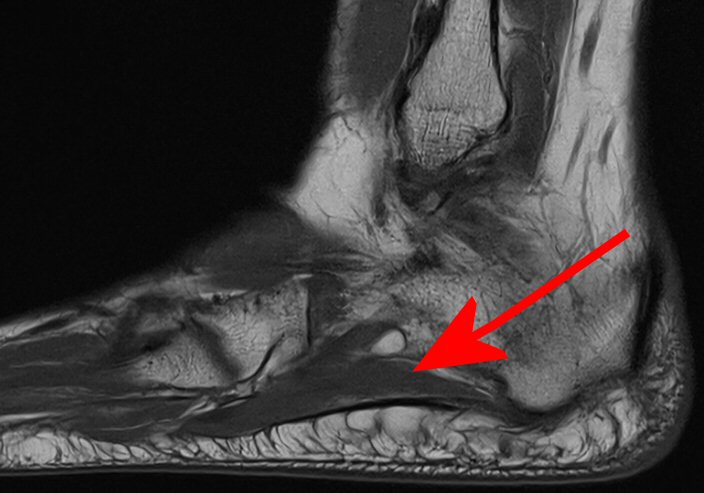

Klinisk diagnos, vid behov MR som visar atrofi av m. abduktor digiti minimi.

Abduktor digiti minimi, här normal, inte atrofierad